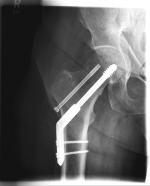

Oberschenkel 5

Picture: In this pertrochanteric femur fracture, a gamma nail was used to stabilize the fracture. The femoral head does not have to be replaced in this case, because the femoral neck is intact and the femoral head is still well supplied with blood.

Pertrochanteric fractures, which are not femoral neck fractures close to the hip, are treated with a so-called gamma nail. The rupture here runs through the large and / or small "hillock" (trochanter major and minor) of the thighbone. Here, due to the location of the fracture, the blood supply to the femoral head is NOT compromised. After the operation, an immediate mobilization can take place under pain-adapted full load.